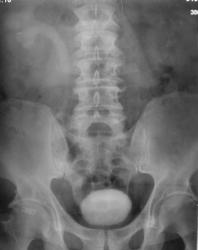

Пациент с диагнозом "МКБ" направлен на обзорную рентгенографию почек и мочевыводящих путей.

Пациент с диагнозом "МКБ" направлен на обзорную рентгенографию

На мой взгляд дополнительная интенсивная тень лежит за контуром почки. В проекции Желчного пузыря. Так что желчекаменная болезнь? Рекомендованно УЗИ печени и желчного пузыря.

Да с камнем желчного то все понятно...но вот тень в проекции н\трети правого мочеточника ....весьма необычна...вопрос - куда ее "пристроить"?))))

Я не про "утверждаю", Боже спаси, для мочеточника тень очень больших размеров, хотя расположена вдоль его проекционной оси, но здесь же проекция крупных сосудов, стенты сейчас могут быть всякими разными, а потом-в малом тазу не только у женщин, но и мужчин хватает всякого, что может обызвествляться. А верхняя тень-типично для желчного пузыря.

Да, камешек для желчного типичный.

А тень в дистальной трети мочеточника действительно "фердиперсовая"...

Признавайтесь, куда делась средняя треть правого мочеточника? Ее как-будто ножом отрезали под линейку, а ниже-сплошное безобразие! "ЧТО" может как обезобразить орган-банальная МКБ с частичной обтурацией просвета или опухоль? А в пузыре тоже камни?

Вы правы, камней не много, их - до "фига"...

А деформация мочевого пузыря никого не смущает?

Отчего же не смущает?))) смущает...она и есть первопричиной образования ТАКОГО камня в мочеточнике, теперь об этом можно сказать с уверенностью, ее генез - выраженое увеличение размеров простаты.